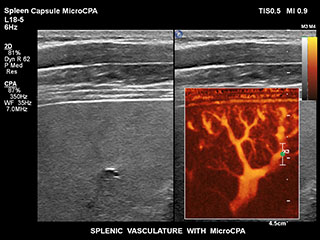

Bisher war die Erfassung von Flussdaten bei kleinen Gefäßstrukturen mit niedriger Flussrate schwierig. Die neue EPIQ Funktion MicroCPA bietet eine schnelle und einfache Darstellung von Mikrozirkulation mit niedriger Geschwindigkeit und ermöglicht eine hohe Diagnosesicherheit bei der Beurteilung der Organperfusion oder von kleinen Gefäßbetten.